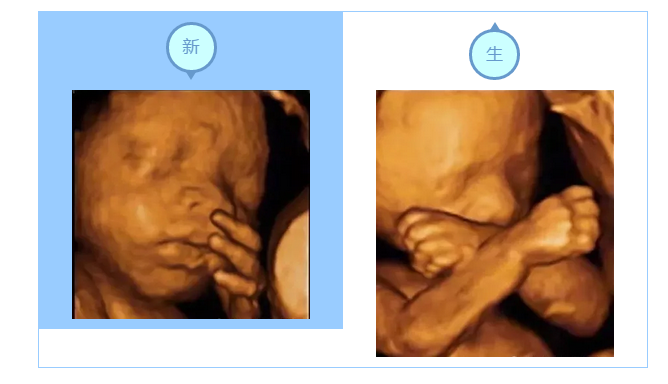

四维彩超的成像是动态的,医生能多方位、多角度、更准确的观察到宝宝的状态和生长发育情况。还能让宝宝和爸爸妈妈提前见面哦~!

为宝宝留下0岁纪念

四维彩超除了有超强的排畸功能之外,还有强大的拍摄功能,能抓捕胎儿的每个细小的动作。